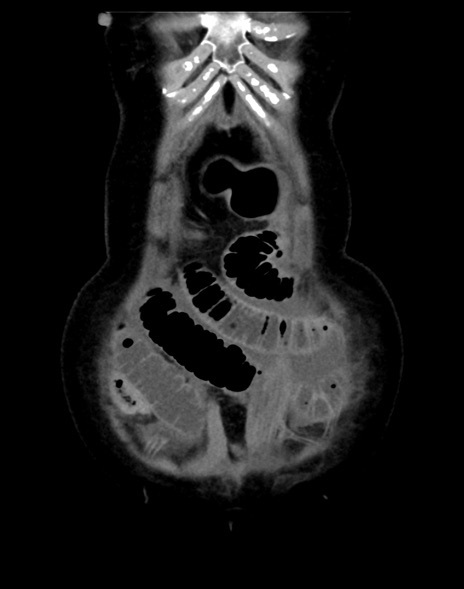

症例13 CT(冠状断像)1日半後